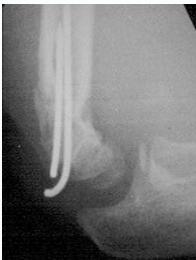

Case Example: 6-year-old girl, fell from swing

After reduction